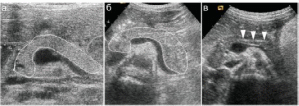

У новорожденного размеры головки, тела и хвоста примерно одинаковые, в старшем возрасте тело значительно тоньше головки и хвоста. Эхогенность паренхимы у новорожденного значительно выше, чем эхогенность печени, в последующем эхогенность паренхимы поджелудочной железы снижается и превышает эхогенность паренхимы печени, структура однородная. Вирсунгов проток не расширен, просвет не визуализируется, иногда могут визуализироваться сомкнутые стенки в виде 2 тонких параллельных линий.

Рисунок Ультрасонограмма поджелудочной железы: а) новорожденный (все части одинаковой величины); б) ребенок 9 лет, тело значительно тоньше других частей; в) вирсунгов проток.